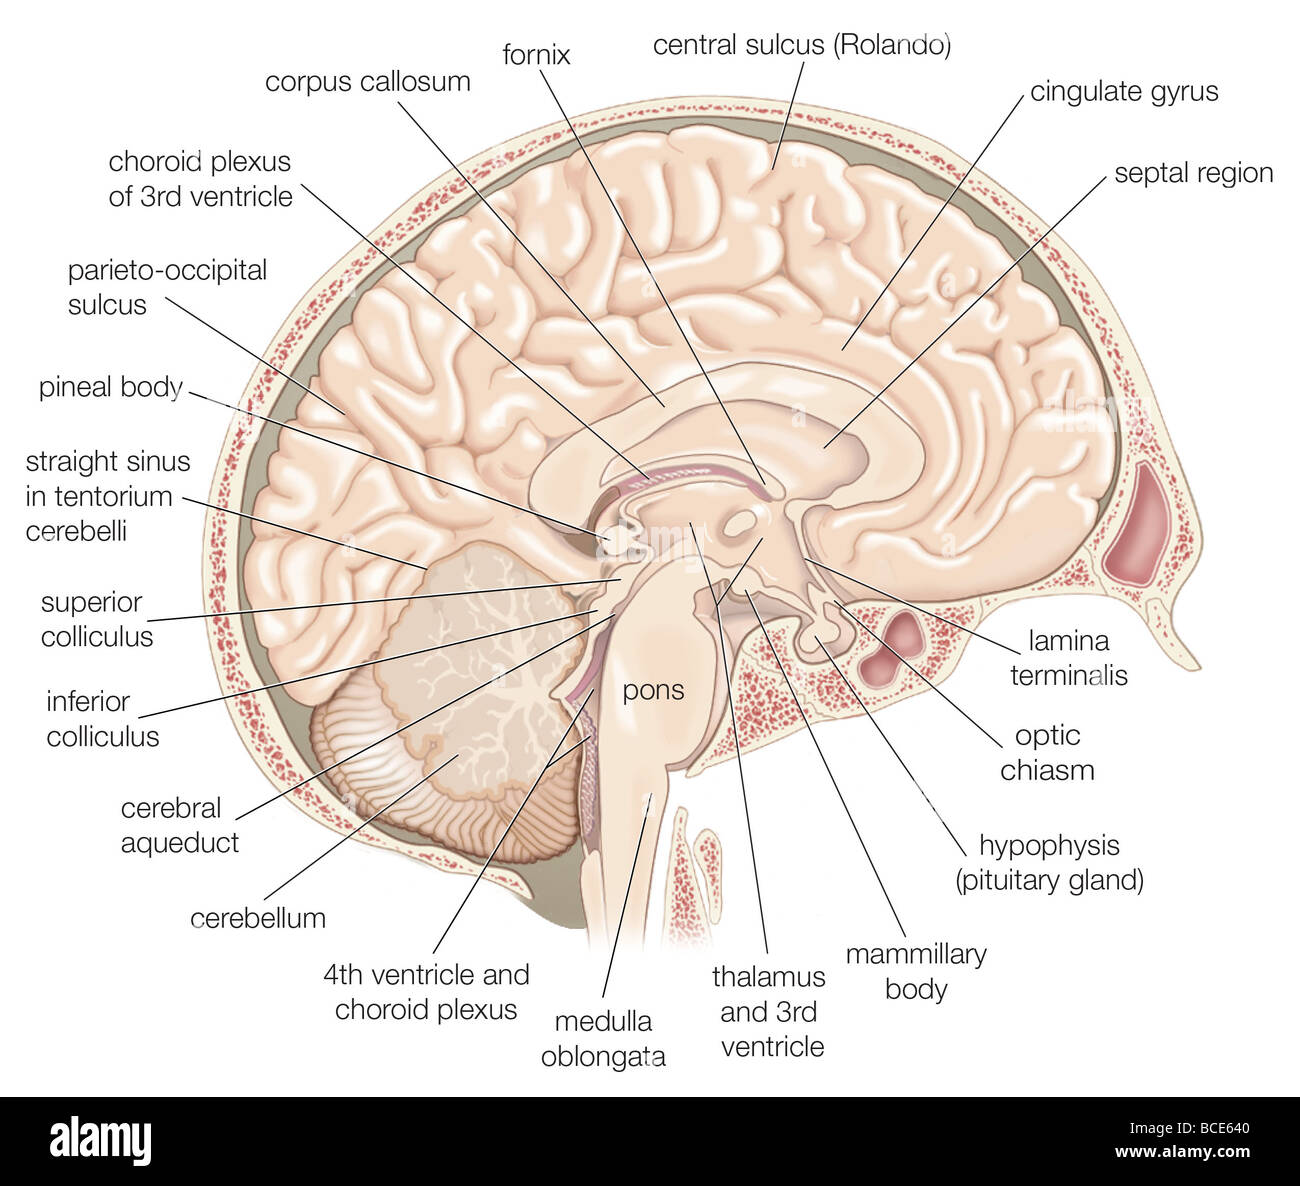

RMPFYB74–. Cunninghams Lehrbuch der Anatomie. Anatomie. PAETS abgeleitet aus dem ZWISCHENHIRN. 617 davon, welche das Aquädukt umgibt, ist direkt kontinuierlich mit der grauen Substanz der substantia perforata posterior und Tuber cinereum, und auf diese Weise kommt es zu der Oberfläche in der Unterseite des Gehirns. Die optic Chiasma kreuzen den Boden vor und markiert die Stelle, wo der Letzteren stetig mit der anterioren Wand des Hohlraums wird. Die vordere Wand des dritten Ventrikels wird durch die Lamina terruinalis, die sich nach oben erstreckt sich von der Optic chiasma gebildet. Die anteriore com-missure, wie es kreuzt von einem

RMBCE641–Sagittale Abschnitt des menschlichen Gehirns, Darstellung von Strukturen der zerebralen Ventrikel, Kleinhirn und Hirnstamm.